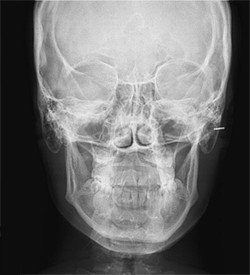

Ortho X - Telerradiografia Frontal

É utilizada para visulaização de septo nasal e da linha mediana e indicada também para localização e demilitação de áreas patológicas.